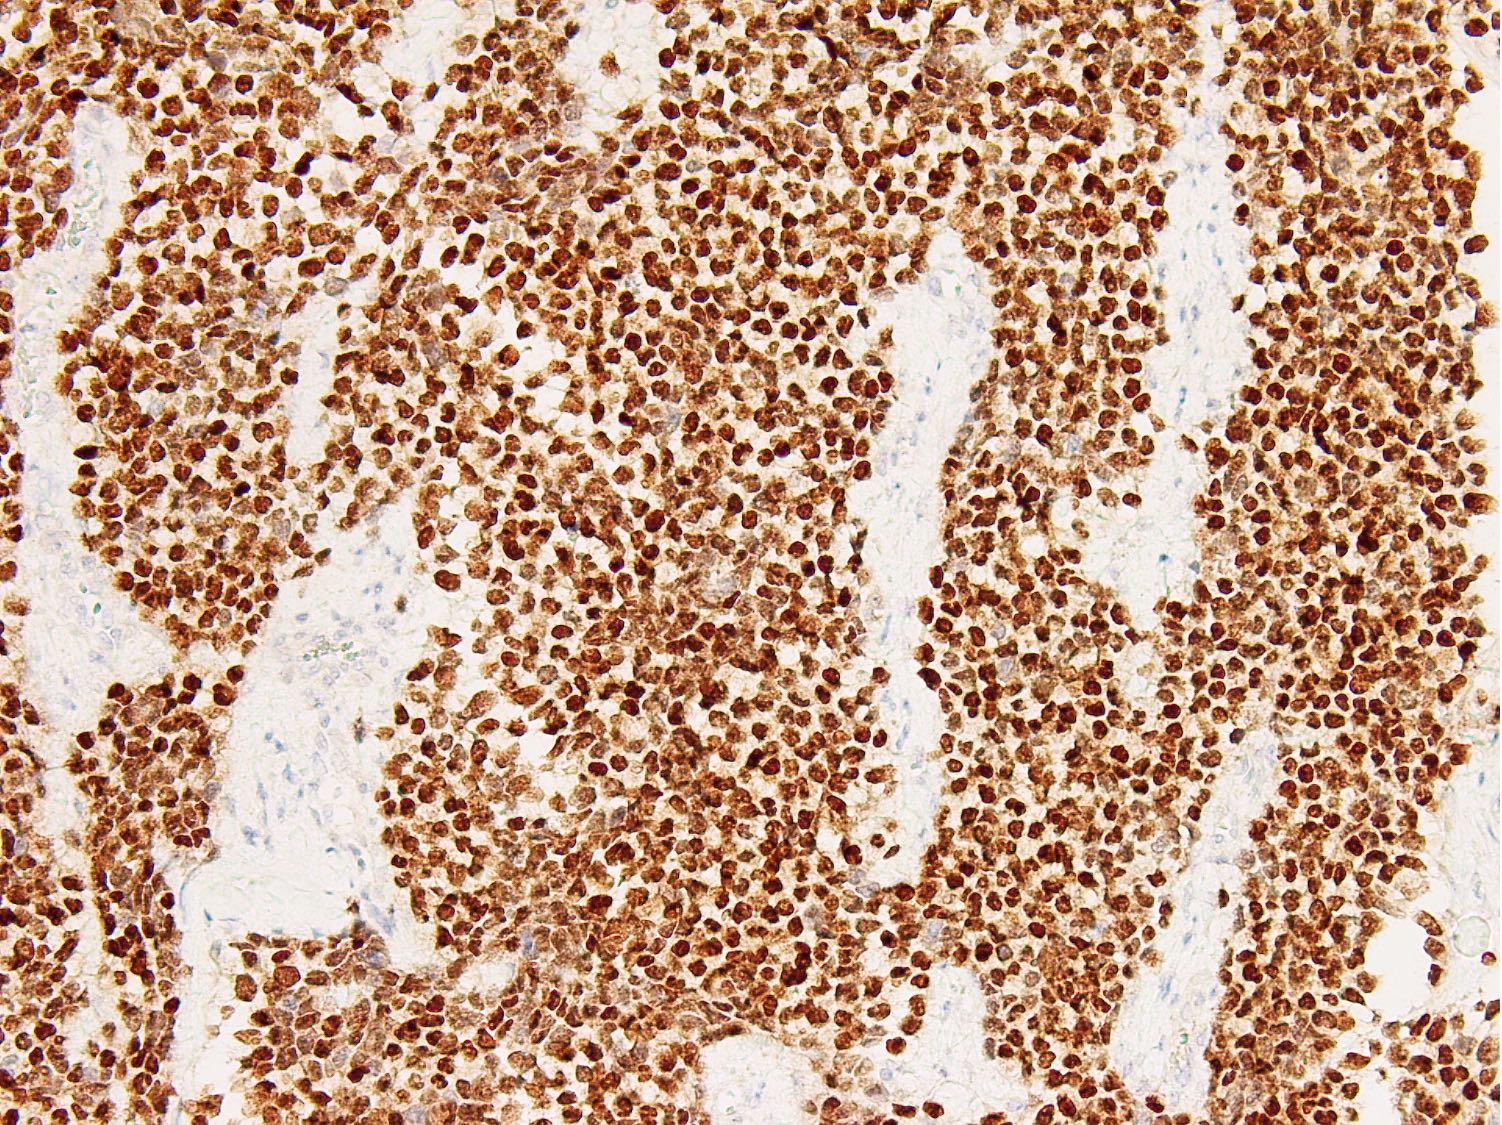

Microscopic (histologic) images

Contributed by Nasir Ud Din, M.B.B.S.

Positive stains

- Stains for myogenic differentiation:

- Desmin

- Myogenin (strong and diffuse) (Ann Diagn Pathol 2018;36:50)

- Diffuse myogenin expression is an unfavorable prognostic factor (Am J Surg Pathol 2008;32:1513)

- Diffuse strong myogenin expression

- Uniform round cells with or without alveolar growth pattern, diffuse homogenous expression of myogenin; heterogeneous expression for desmin or MyoD1; detection of PAX3::FOXO1 / PAX7::FOXO1 fusion by molecular analysis